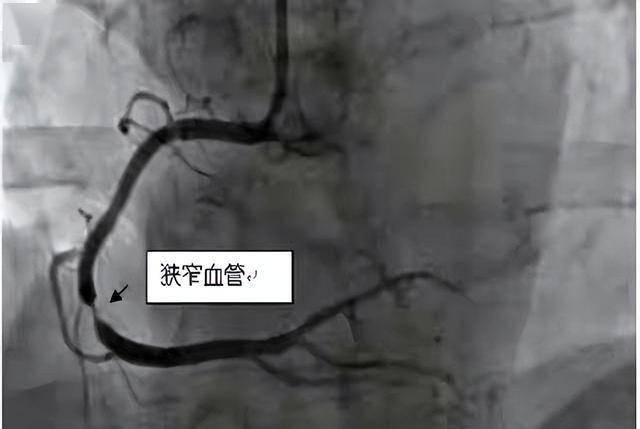

就像这次,男子出现胸痛去医院,医生只排除了感冒,却没有做心电图、心脏彩超或更深入的检查。

冠脉造影、24小时动态心电图这些项目,成本高、操作复杂,一般人只要没什么大问题,医生根本不会主动安排。